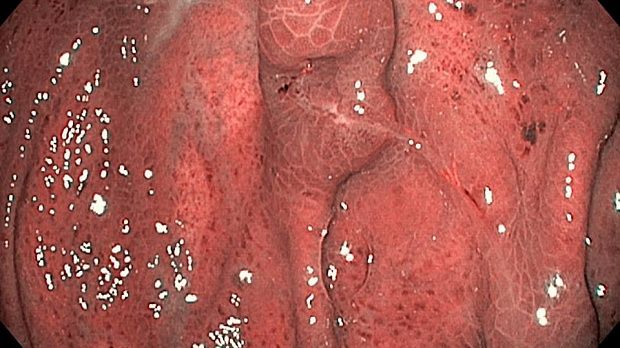

Публикации из социальных сетей: “Cobblestone esophagitis” (эзофагит со слизистой булыжной мостовой)

“Cobblestone esophagitis” (эзофагит со слизистой булыжной мостовой) - редкая эндоскопическая находка и ассоциируется с эозинофильным эзофагитом, кандидозом и пищеводом Барретта у взрослых. Он также может быть найден при тяжелом рефлюкс-эзофагите, вторичен к дистальной обструкции гастроинтестинального тракта. В нашем случае - это пациент после с 9-летним стажем бандажирования кардиального отдела желудка, признаками дуоденостаза, фундальной эрозивной гастропатией, расширением пищевода и уровнем жидкости в нем при горизонтальном положении, грыжи ПОД, эрозивно-язвенном дистальном эзофагите.. Пациент просто пришел удалить полип в прямой кишке и заодно посмотреть, что творится в желудке.... Ацетообеление+NBI+биопсия. ИПП на 3-4 мес и повтор для решения о Барретте.